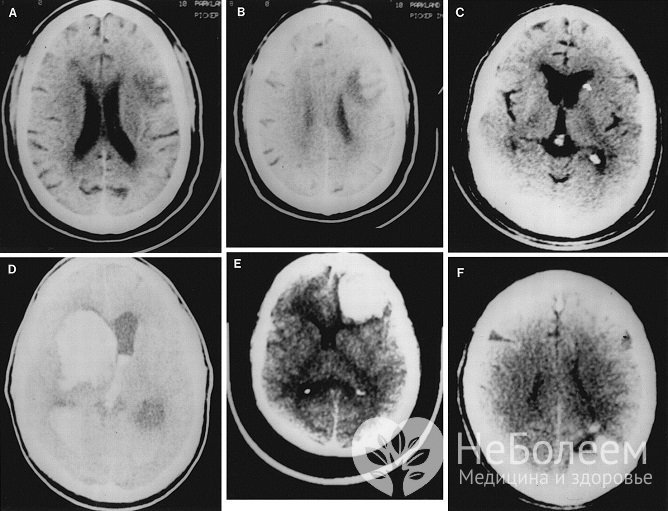

Диагноз должен быть поставлен в максимально сжатые сроки. Используется инструментальная диагностика. Точным и эффективным методом является компьютерная томография, поскольку она дает возможность отличить кровоизлияние от инфаркта в большинстве случаев. Также применяется магнитно-резонансная томография, однако разница методов заключается в том, что МРТ не используется для экстренной диагностики. Для изучения состояния сосудов применяют дуплексное сканирование и допплерографию.